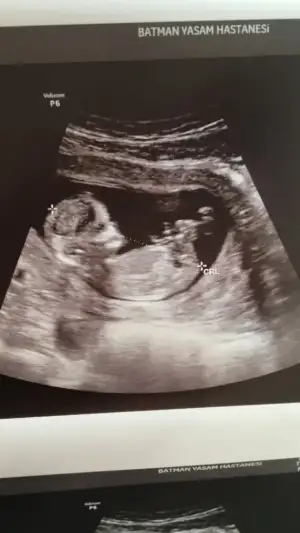

Bizim içinde yorum yapabilir misiniz 12+4 🥰 karından ultrason resimleri bunlar